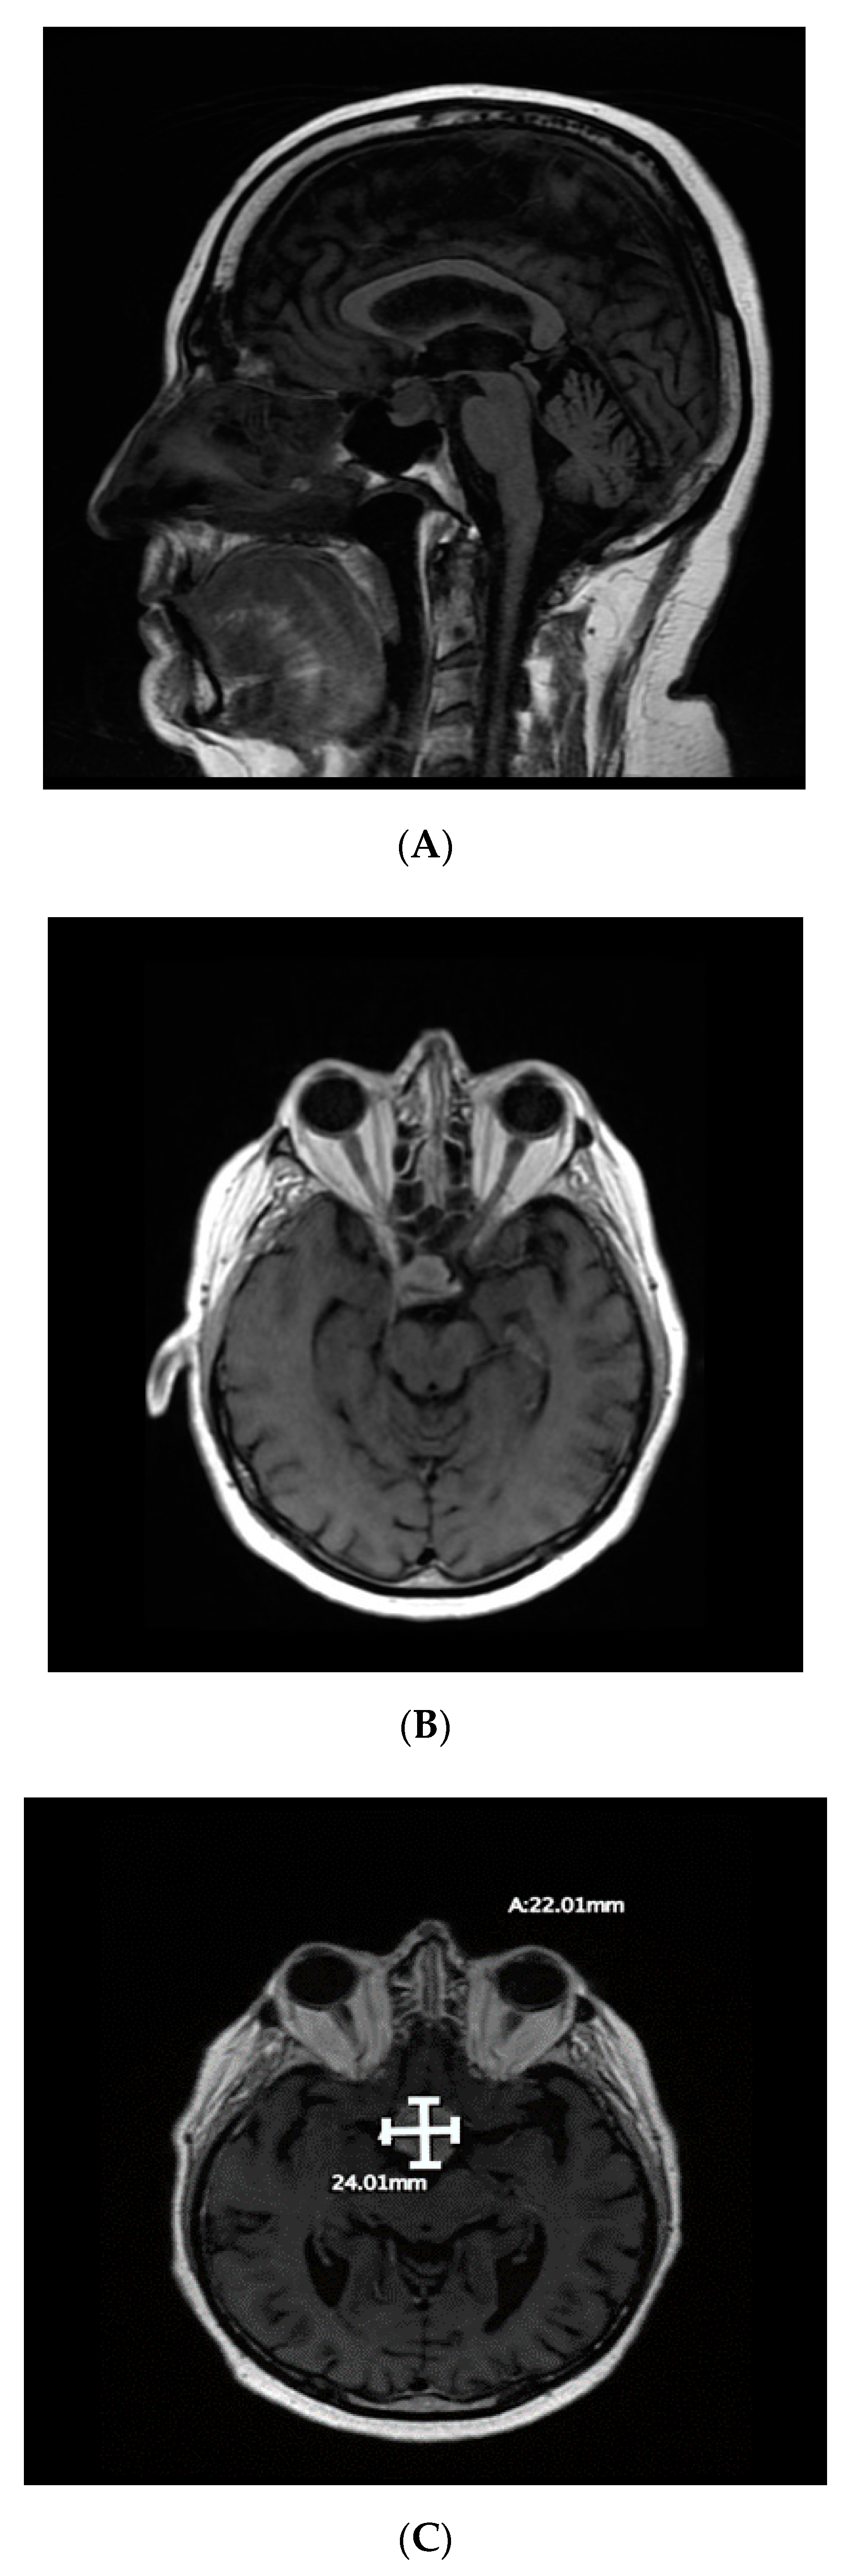

The patient developed a headache in May 2018. Brain magnetic resonance imaging (MRI) in June 2018 showed a new lesion in the right sellar region measuring 2.12 × 1.4 × 1.2 cm, extending to the suprasellar space and rising from the infundibulum and/or posterior pituitary gland (Figure 1). Two differential diagnoses were considered: prostate metastasis to the pituitary sella and incidental pituitary nonsecreting adenoma. The patient’s PSA level had then risen to 290 ng/mL (Figure 2), which suggested that the first option was the more likely diagnosis.

By August 2018, the patient had developed bitemporal hemianopsia and decreased visual acuity, which progressed to complete visual loss. Transnasal transsphenoidal endoscopic resection of the mass was performed in September 2018, and navigation MRI performed during surgery revealed that the initial lesion had doubled in size, and that there was another right temporal lesion. Surgical excision was subtotal (Figure 3). Final pathology results indicated that the most likely diagnosis was metastatic adenocarcinoma, consistent with a prostatic primary tumor (sellar tumor). After surgery, more brain lesions were identified in the hypothalamus extending into the right basal ganglia and a dural base lesion.

Metastatic tumors in the pituitary usually grow more rapidly than primary tumors do in this area [6,7]. For our patient, the pituitary metastatic tumor doubled in size within two months, consistent with this finding. The doubling in size of the tumor was also a confirmation of the diagnosis, as this increase in size is consistent with disease progression.

Figure 1. (A,B) Preoperative magnetic resonance imaging of the brain (June 2018) revealing a right sellar mass approximately 2.12 × 1.4 × 1.2 cm in size (A: sagittal view; B: axial view); (C) imaging during surgery in September 2018 showed that the mass had increased in size.